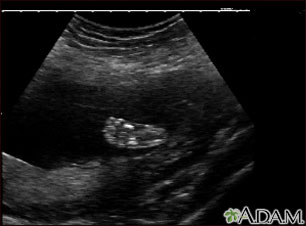

Ultrasonido normal a las 19 semanas de gestación. En la parte central de la pantalla se ve claramente el pie derecho, así como los huesos en formación.